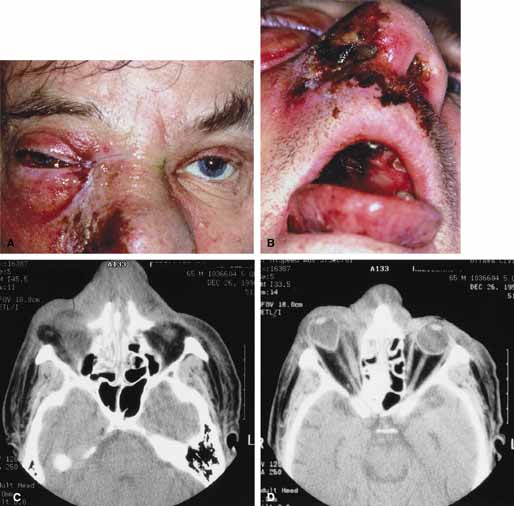

Secondary orbital tumors such as malignant tumors of the sinus (e.g., squamous cell carcinoma) may abruptly involve the orbit producing acute proptosis over 1 to 2 days with lid swelling, chemosis, motility disturbance, and pain (Fig. 14A and 14B). Diagnosis is confirmed by CT imaging and biopsy of the tissue.

Fig. 14 A. A 43-year-old male presented with a 2-day history of right upper eyelid swelling. B. Axial computed tomography (CT) scan revealed a mass in the right frontal sinus with extension into the right orbit. A biopsy disclosed poorly differentiated squamous cell carcinoma.